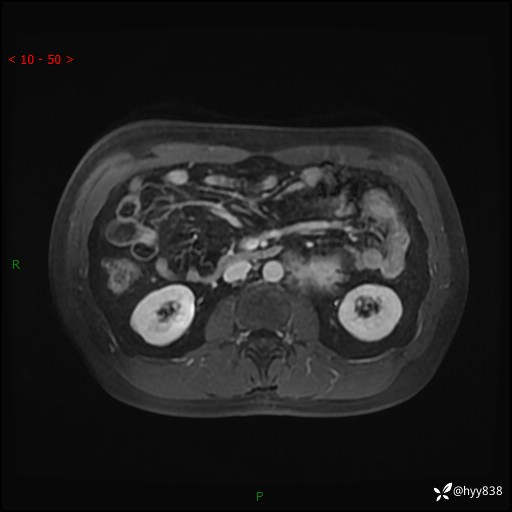

现病史:患者3月余前检查发现左侧腹膜后占位,大小约3.7*4.9cm,平素无腰疼,无肉眼血尿,无尿频尿急等不适,当时未特殊处理,在门诊复查CT提示左侧腹膜后占位,门诊拟“左侧腹膜后占位”收入院。 起病以来,患者精神佳,饮食、睡眠良好,大小便正常,体力体重无明显变化。

MRI增强